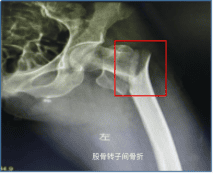

三、需要进行哪些辅助检查?

X片: CT: